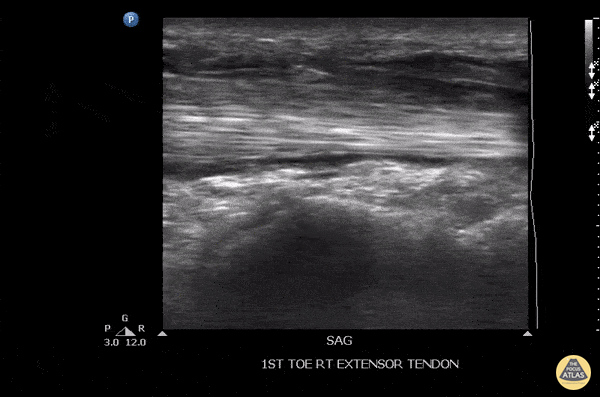

Musculoskeletal - Tenosynovitis Of The Extensor Hallucis Longus Tendon

Patient initially suffered a puncture wound 8 days ago to the top of the foot. He presented a week later with pain in the toe, especially with flexion. US imaging showed extensive fluid surrounding the extensor hallucis longus tendon consistent with infectious tenosynovitis. The patient was taken to OR for debridement with good outcome. Image courtesy of Robert Jones DO, FACEP @RJonesSonoEM Director, Emergency Ultrasound; MetroHealth Medical Center; Professor, Case Western Reserve Medical School, Cleveland, OH View his original post here